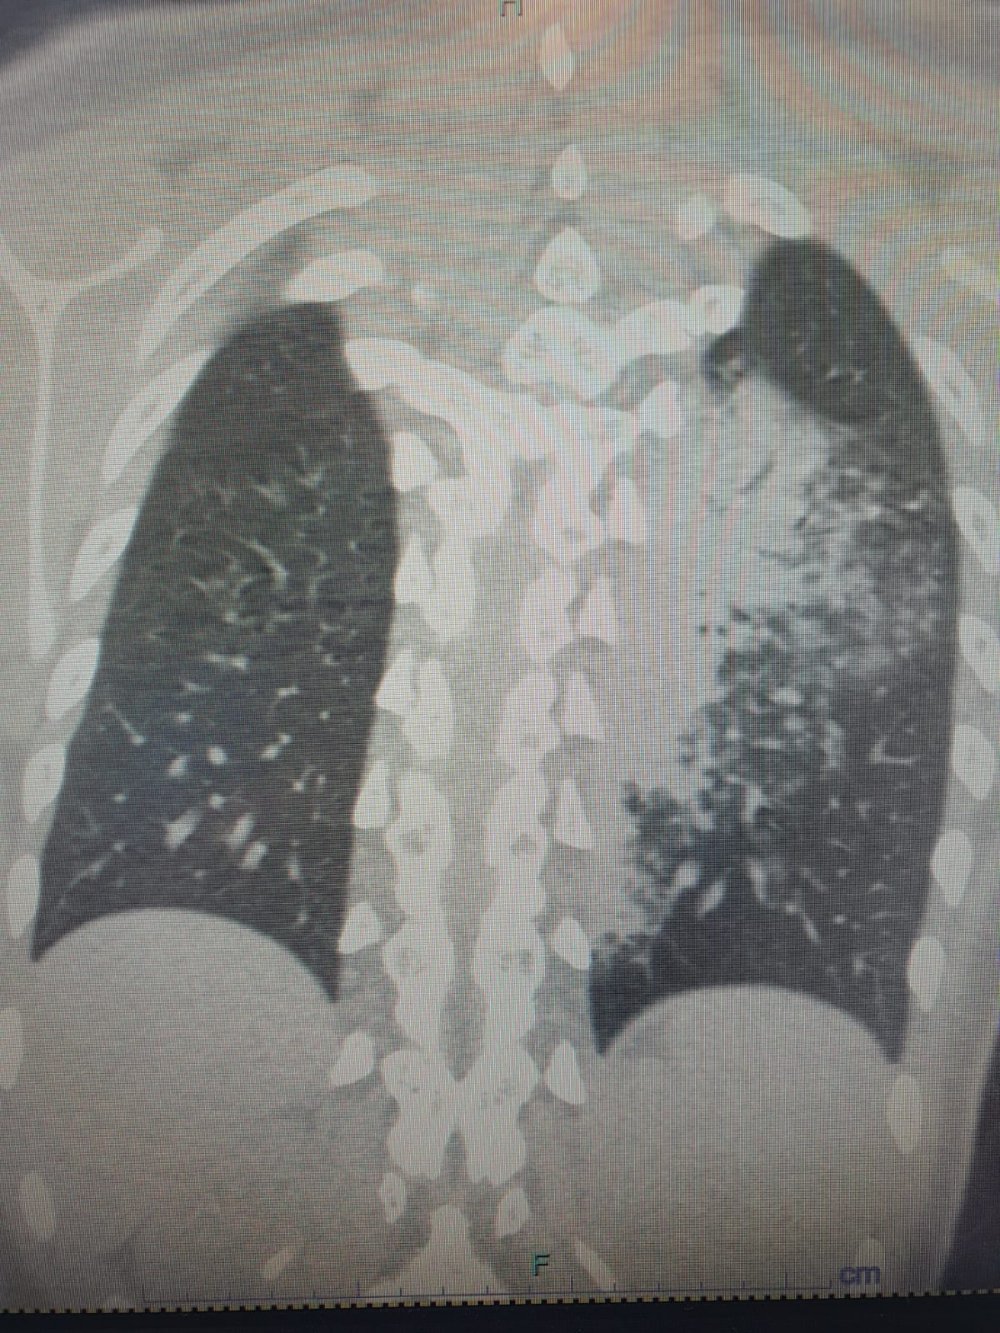

Göğüs Hastalıkları Uzmanı Prof. Dr. Şevket Özkaya, özellikle otel ve tatil köylerinde konaklayan kişiler arasında “beni klima çarptı” diyen neredeyse her iki kişiden birinde bu hastalıkların saptandığını belirtti. Prof. Dr. Özkaya, bu durumdan en çok etkilenenlerin ise çocuk yaş grubu olduğunu vurgulayarak, “Ciddi sayıda, daha önce görülmemiş derecede çocuk bronşiti ve zatürresi vakaları görmeye başladık. Hatta COVID-19 salgınında, çocuk yaş grubunda COVID-19 virüsüne bağlı bu kadar çok zatürre görmüyorduk. Son günlerde; ‘Legionella’ bakterisinin, çocuk yaş grubunda COVID-19’a oranla çok daha fazla zatürreye neden olduğunu görüyoruz,” diyerek durumun ciddiyetine dikkat çekti.

Lejyoner hastalığı adı verilen ve Legionella pneumophila isimli bakterinin klimalardan üremesi sonucunda ortaya çıktığını belirten Prof. Dr. Özkaya, bu hastalığın kronik rahatsızlığı olanlarda ölümcül olabileceğini ve yaşlı, kronik hastalığı olan vatandaşların dikkatli olmaları gerektiğini hatırlattı.

Özellikle klimaların iyi temizlenmesi gerektiğini belirten Prof. Dr. Özkaya, klima zatürresinde şikayetlerin daha az olduğu için grip gibi eklem ağrıları, ateş, halsizlik, ishal gibi hafif soğuk algınlığı belirtileriyle seyrettiği için çok fazla anlaşılmayabileceğini söyledi. Kronik hastalığı olanlarda hayati sonuçlar da doğurabileceğini belirten Özkaya, “Pandeminin bitmesiyle beraber ani ısı değişikliklerine, soğuktan sıcağa geçişlere ve klimalara maruz kalmak, grip ile karıştırılabilinir ve önemsenmeyebilir. Çocukların ise ne hissettiklerini anlatamadıkları için uzamış öksürük ve ateş şikayeti ile doktora başvurduklarında ciddi zatürre vakaları ile karşı karşıya kalırlar” dedi.